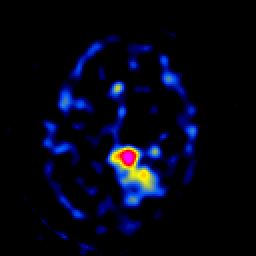

SPECT TL Study #7 -- Slice #40